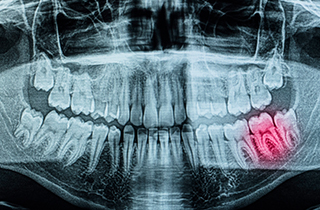

Caries treatment for decay detected on X-ray imaging

Various Diagnostic Methods for Dental Caries

After carefully evaluating the condition of a tooth affected by decay, we recommend the treatment that is best for the tooth.